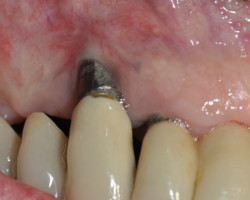

Nécessité d’avoir un bandeau de gencive kératinisée de 2mm minimum pour pouvoir assurer une hygiène correcte et une stabilité des tissus mous péri-implantaire (Lin et al 2013).

Dépose de l’implant